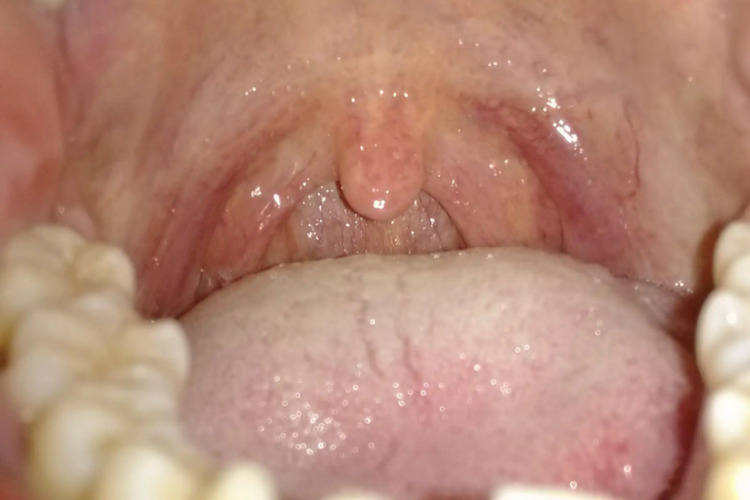

平时所说的嗓子,更多关注的是位于腭帆游离缘与会厌上缘平面之间的口咽部分,因为鼻咽和口咽部分不易用肉眼观察到。口咽的侧壁上有腭扁桃体,位于扁桃体窝内,呈椭圆形。正常情况下咽部黏膜没有充血、红肿现象,而且没有表面粗糙、淋巴滤泡呈簇状的表现。扁桃体不会红肿、增大,扁桃体隐窝内没有分泌物。